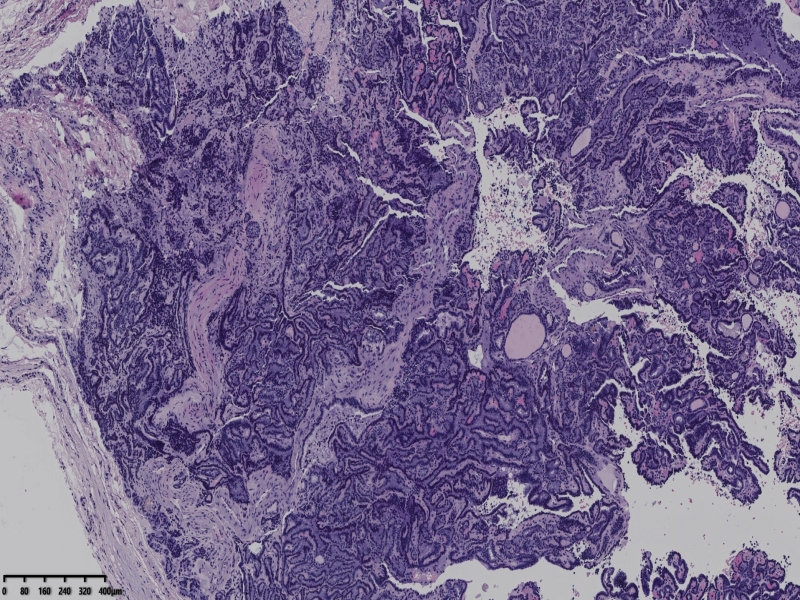

男、69、甲状腺左叶肿物,部分为囊性,囊内可见乳头状结构,上皮核重叠,没有核沟,没有毛玻璃样改变,没有核内假包涵体。255427

部分区域瘤组织与周围甲状腺组织分界明显,没有包膜样结构,滤泡结构为主,细胞异型明显。

会诊结果:(左叶甲状腺近峡部)甲状腺肿瘤,考虑为具有RAS核的乳头状癌,建议免疫组化及基因检测。